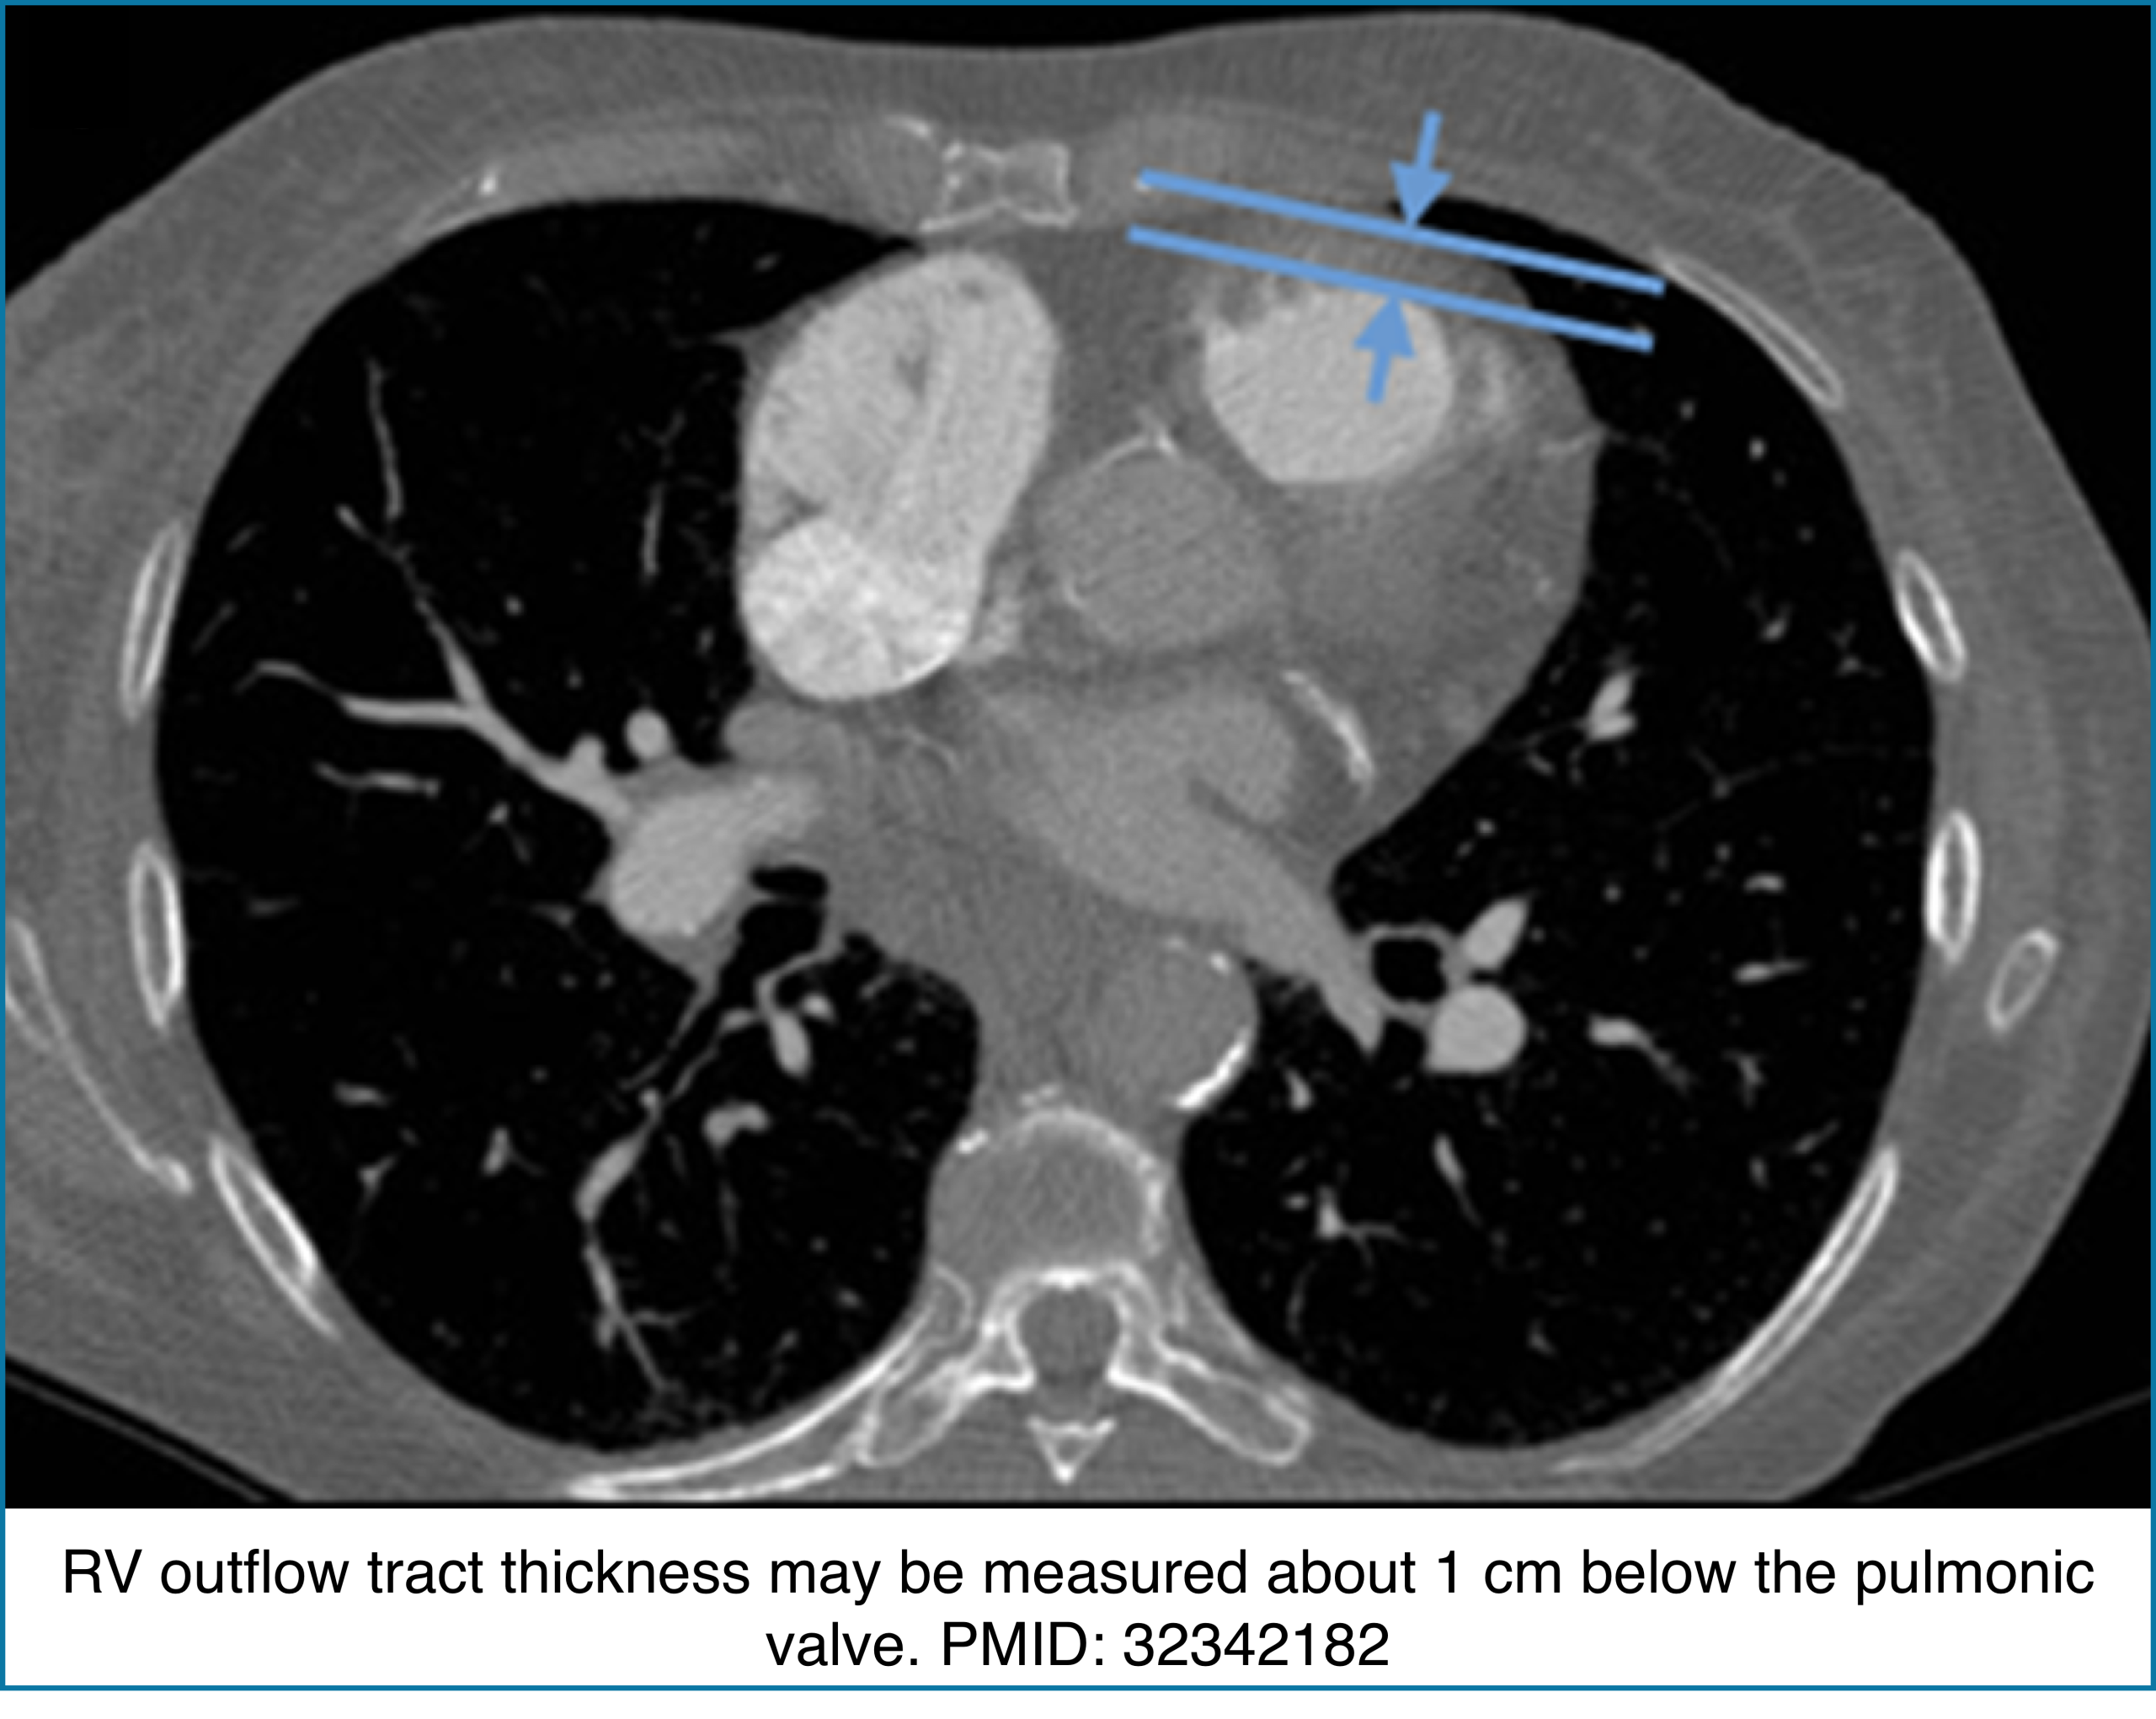

◾️Right Ventricular Wall Thickness

- The RV normally has a very thin free wall that is often difficult to appreciate on CT. When the RV outflow tract becomes visibly thickened, it usually reflects chronic pressure overload rather than acute pathology.

- Key Pearls

- Normal RV wall: Thin, ~3 mm, often barely visible on CT.

- RVOT thickness >6 mm: Suggests chronic pulmonary hypertension.